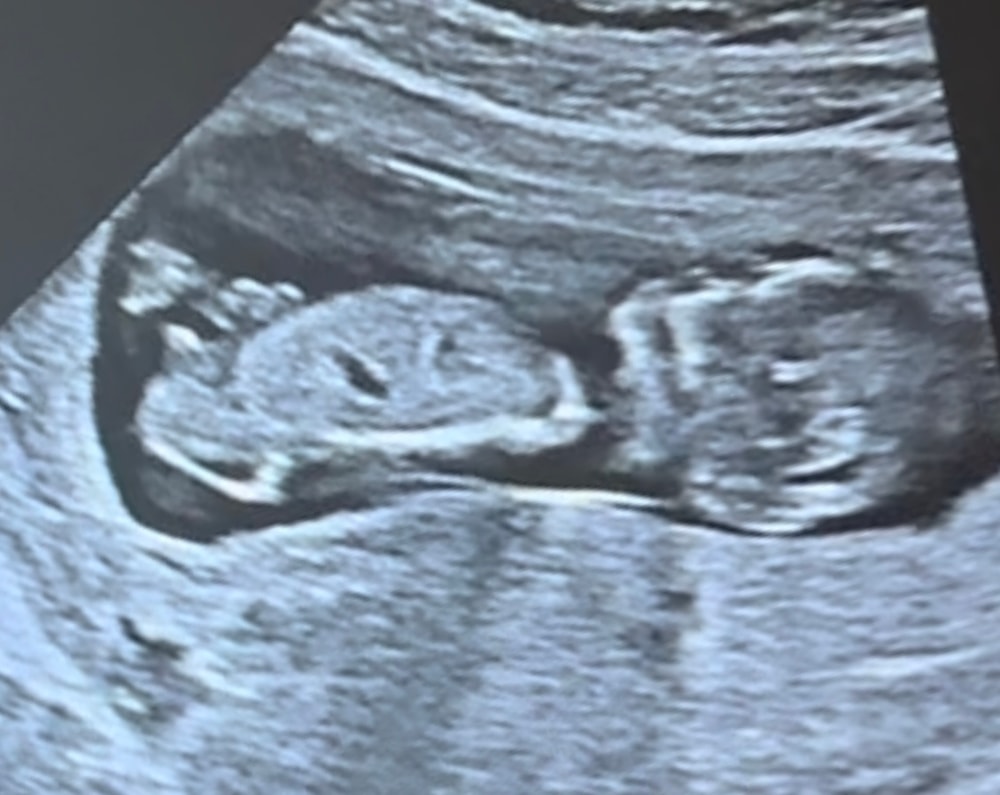

Пол по узи, 1 скрининг

Пол малышаВсем привет. Сходила на первый скрининг. Знаю, что еще рано видеть пол, и что видят только опытные врачи. Но я не удержалась и спросила «не видно ли еще?». Врач сказала «я бы не так не сказала. Я могу сказать, что мальчик не определяется» - показала мне вид снизу. Ну в общем девочка по ее мнению. Но! Я на протяжении узи что-то сняла на видео, а дома до скрининга начиталась и насмотрелась тут на форуме на разницу половых бугорков. В итоге начала разглядывать эти видео, и такое ощущение, что мальчик все-таки определяется)))) Понимаю, что я не врач, но как будто это писюн! Как думаете?

Скрининг был на сроке 12.1 по месячным, по узи поставили 13.1.

вот фото)